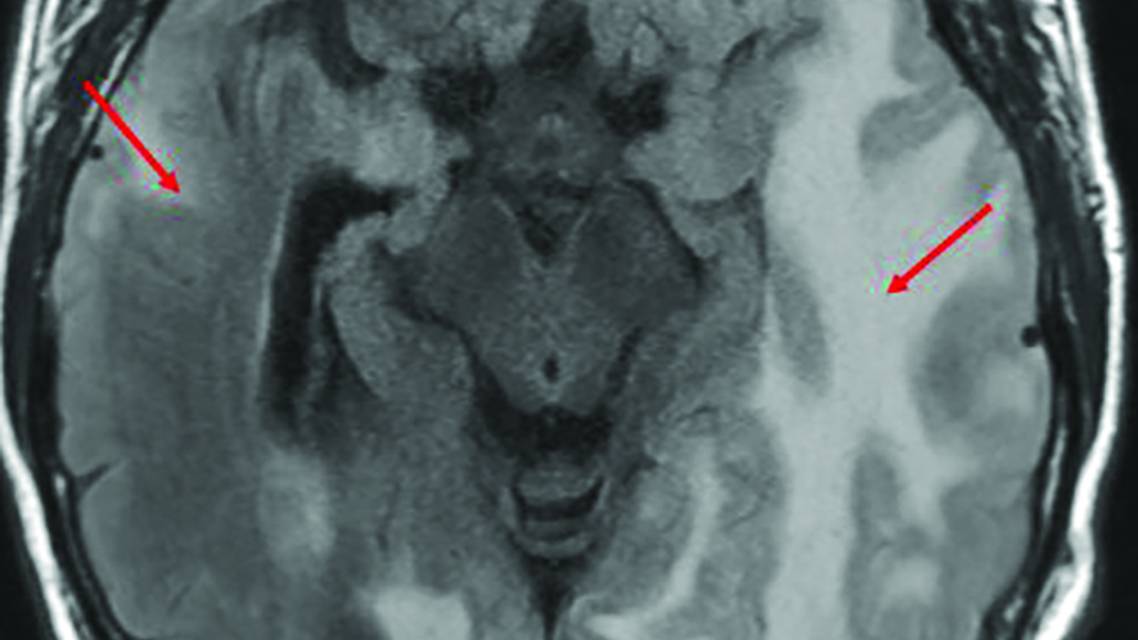

ARIA-E (Figure 1) is characterized by vasogenic edema or sulcal effusion, best seen on fluid-attenuated inversion recovery (FLAIR) MRI sequences. ARIA-E may be seen on MRI scans with no associated clinical symptoms. If symptoms occur, they vary in nature and typically are seen when the amount of edema on the MRI scans involves >5 cm of brain tissue. Common complaints associated with ARIA-E include headaches, confusion, nausea, vomiting, dizziness, visual disturbance, tremor, balance, or gait disturbance. In some cases, ARIA-E can cause seizures or focal neurologic deficits, such as weakness, sensory loss, or other cognitive or language problems.

Figure 1. Axial fluid-attenuated inversion recovery MRI scan demonstrating extensive bilateral temporal-parieto-occipital vasogenic edema (red arrows), consistent with amyloid-related imaging abnormalities with edema, in an individual receiving anti-amyloid therapy. The individual presented with confusion and headache. Clinical and radiologic resolution occurred over several weeks.